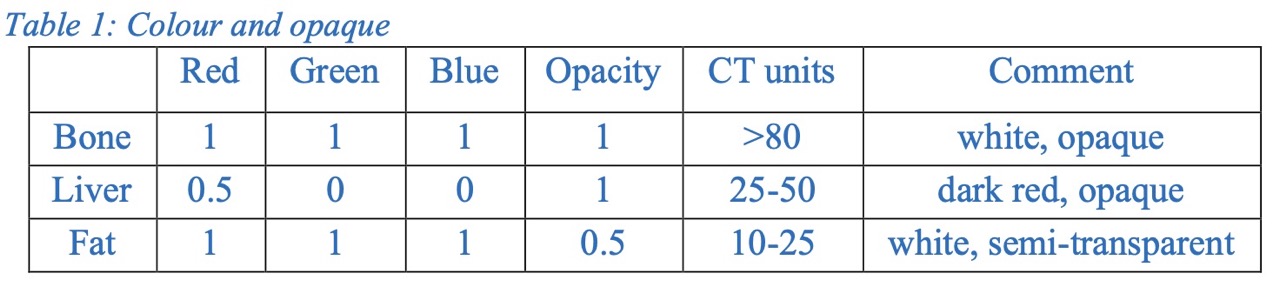

- Transfer Function Design: Created mappings from voxel intensity to RGBA values, enabling anatomical realism in CT renderings (bone, liver, fat).